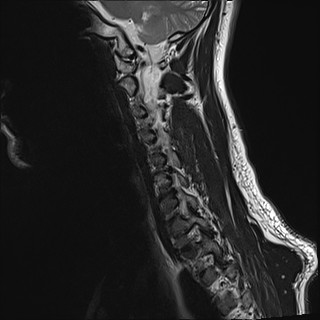

Wirbelsäule HWS

t2_tse_sag